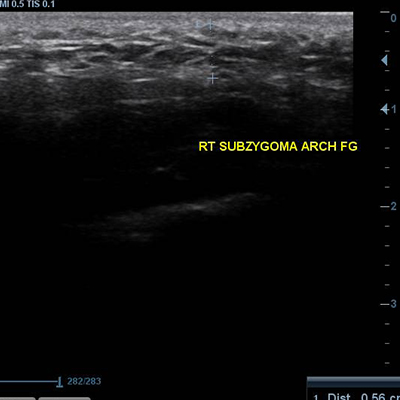

[얼굴이물질제거] 17.01.23 - 이물질제거 - 전후사진

17.01.23 - 이물질제거 - 전후사진